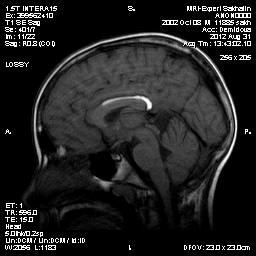

Сегодня проходил исследование ребенок с жалобами на головную боль.В анамнезе-удар головой около 1 мес.назад.Мама сообщила , что при родах на УЗМ выявили кровоизлияние в мозолистое тело, причем сообщила уже после исследования, когда мой мозг был на грани истерии-это уже второй случай за неделю, а я не могу ничего толком понять-это тромбированный сосуд либо кровоизлияние?Обоим рекомендовала проведение МР-ангио.

Липома мозолистого тела. КТ разрешит все сомнения.

может перикаллёзная липома. Надо жироподавление было поставить. тоже разрешит.

Перикаллезные липомы бывают линейные (криволинейные, повторяющие формы мозолистого тела) и узловые.